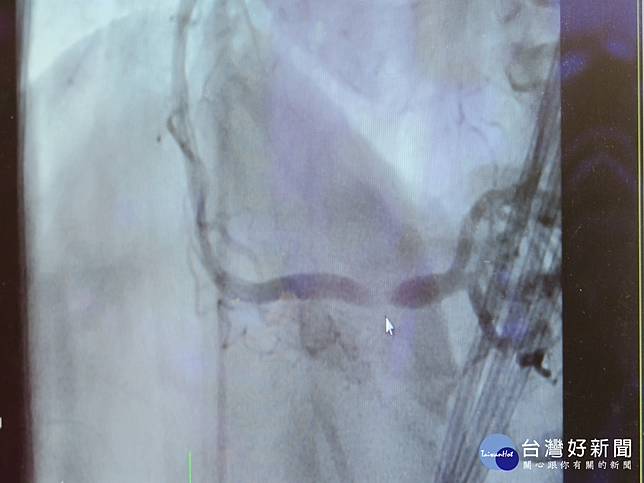

「老天爺給你機會時,千萬不要忽視!」彰化溪湖一位65歲楊洽聞先生在10天內2次胸悶冒冷汗,,等到第3次發病竟是突然失去意識、沒有心跳呼吸,經消防隊、急診及心導管人員10分鐘接力搶救才搶回一命。彰化醫院心臟內科醫師王彥翔指出,病患右冠狀動脈急性心肌梗塞,馬上進行心導管術,放了2支支架,恢復血流順暢。王彥翔說,老天給了病患2次機會,都沒把握機會處理,第3次若非立即發現、快速處理,恐也無力回天。

王彥翔表示,楊先生可能在10天前就已經血栓,那2次的胸悶若能就醫找出其心血管阻塞之處並趕快處理,就不會有第3次的生死搏鬥。從另一個角度來看,如果第3次發作心跳呼吸停止時,是在家裡而沒人發現或是反應過慢,大概也救不回來了,可見上天還是眷顧病患。